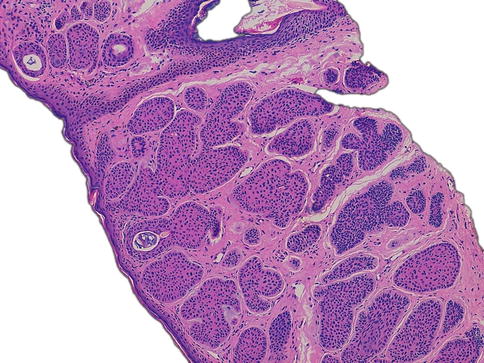

Fig. 7.4

Cryobiopsy. Basal cell carcinoma. Absence of the artifactual changes. Hematoxylin-eosin stained. Original magnification, 100×